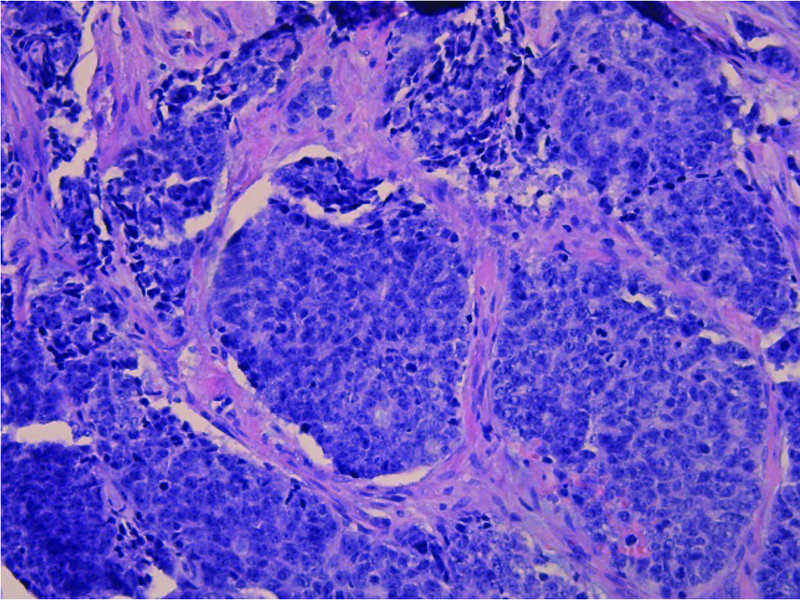

The biopsy showed a biphasic tumor, composed of ductal and myoepithelial cells in a solid pattern with basaloid appearance, high mitotic rate and marked nuclear atypia, supporting high grade transformation (Figure B&C). The tumor was strongly and diffusely positive for immunohistochemical stains CK7 (Figure D) and CD117 (Figure E). Molecular studies were also performed, and the tumor showed t (6;9) MYB-NFIB fusion which is characteristic and diagnostic for adenoid cystic carcinoma in 60–90% of the cases. Overall, the findings were consistent with high-grade adenoid cystic carcinoma, solid type.

Figure B and C. Histologic images (Figure B, 10x and Figure C, 20x) displaying biphasic tumor in sheets and clusters, composed of ductal and myoepithelial cells in solid pattern with basaloid appearance and showing marked nuclear atypia and high mitotic rate; high grade transformation.